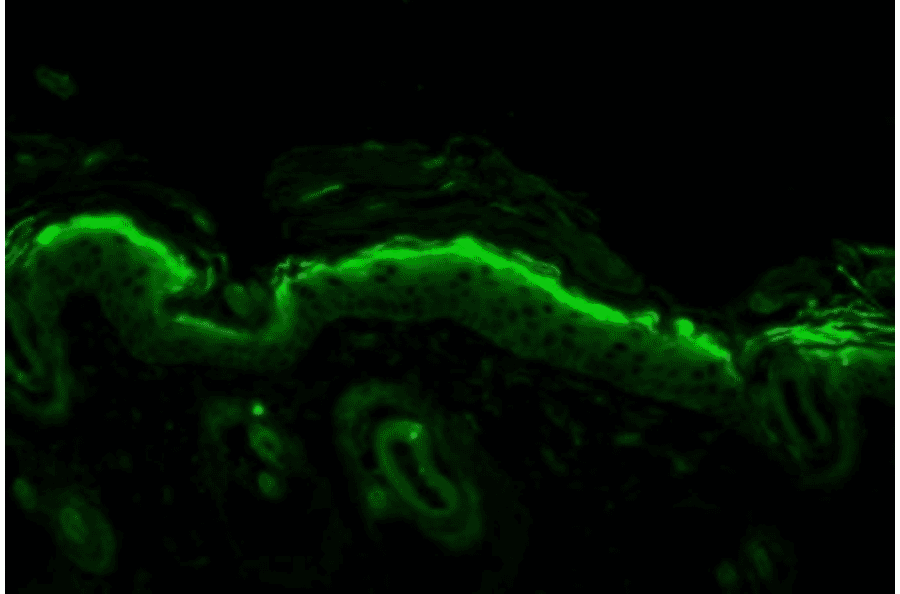

Immunohistochemistry analysis of mouse backskin, fixed in Bouin's fixative solution and paraffin-embedded. The Primary Antibody used was Anti-Nitrotyrosine Antibody [39B6] (A304794) at 1:100 for 1 hour at room temperature. The secondary antibody used was FITC Goat Anti-Mouse (green) at 1:50 for 1 hour at room temperature. Backskin obtained from transgenic mice.